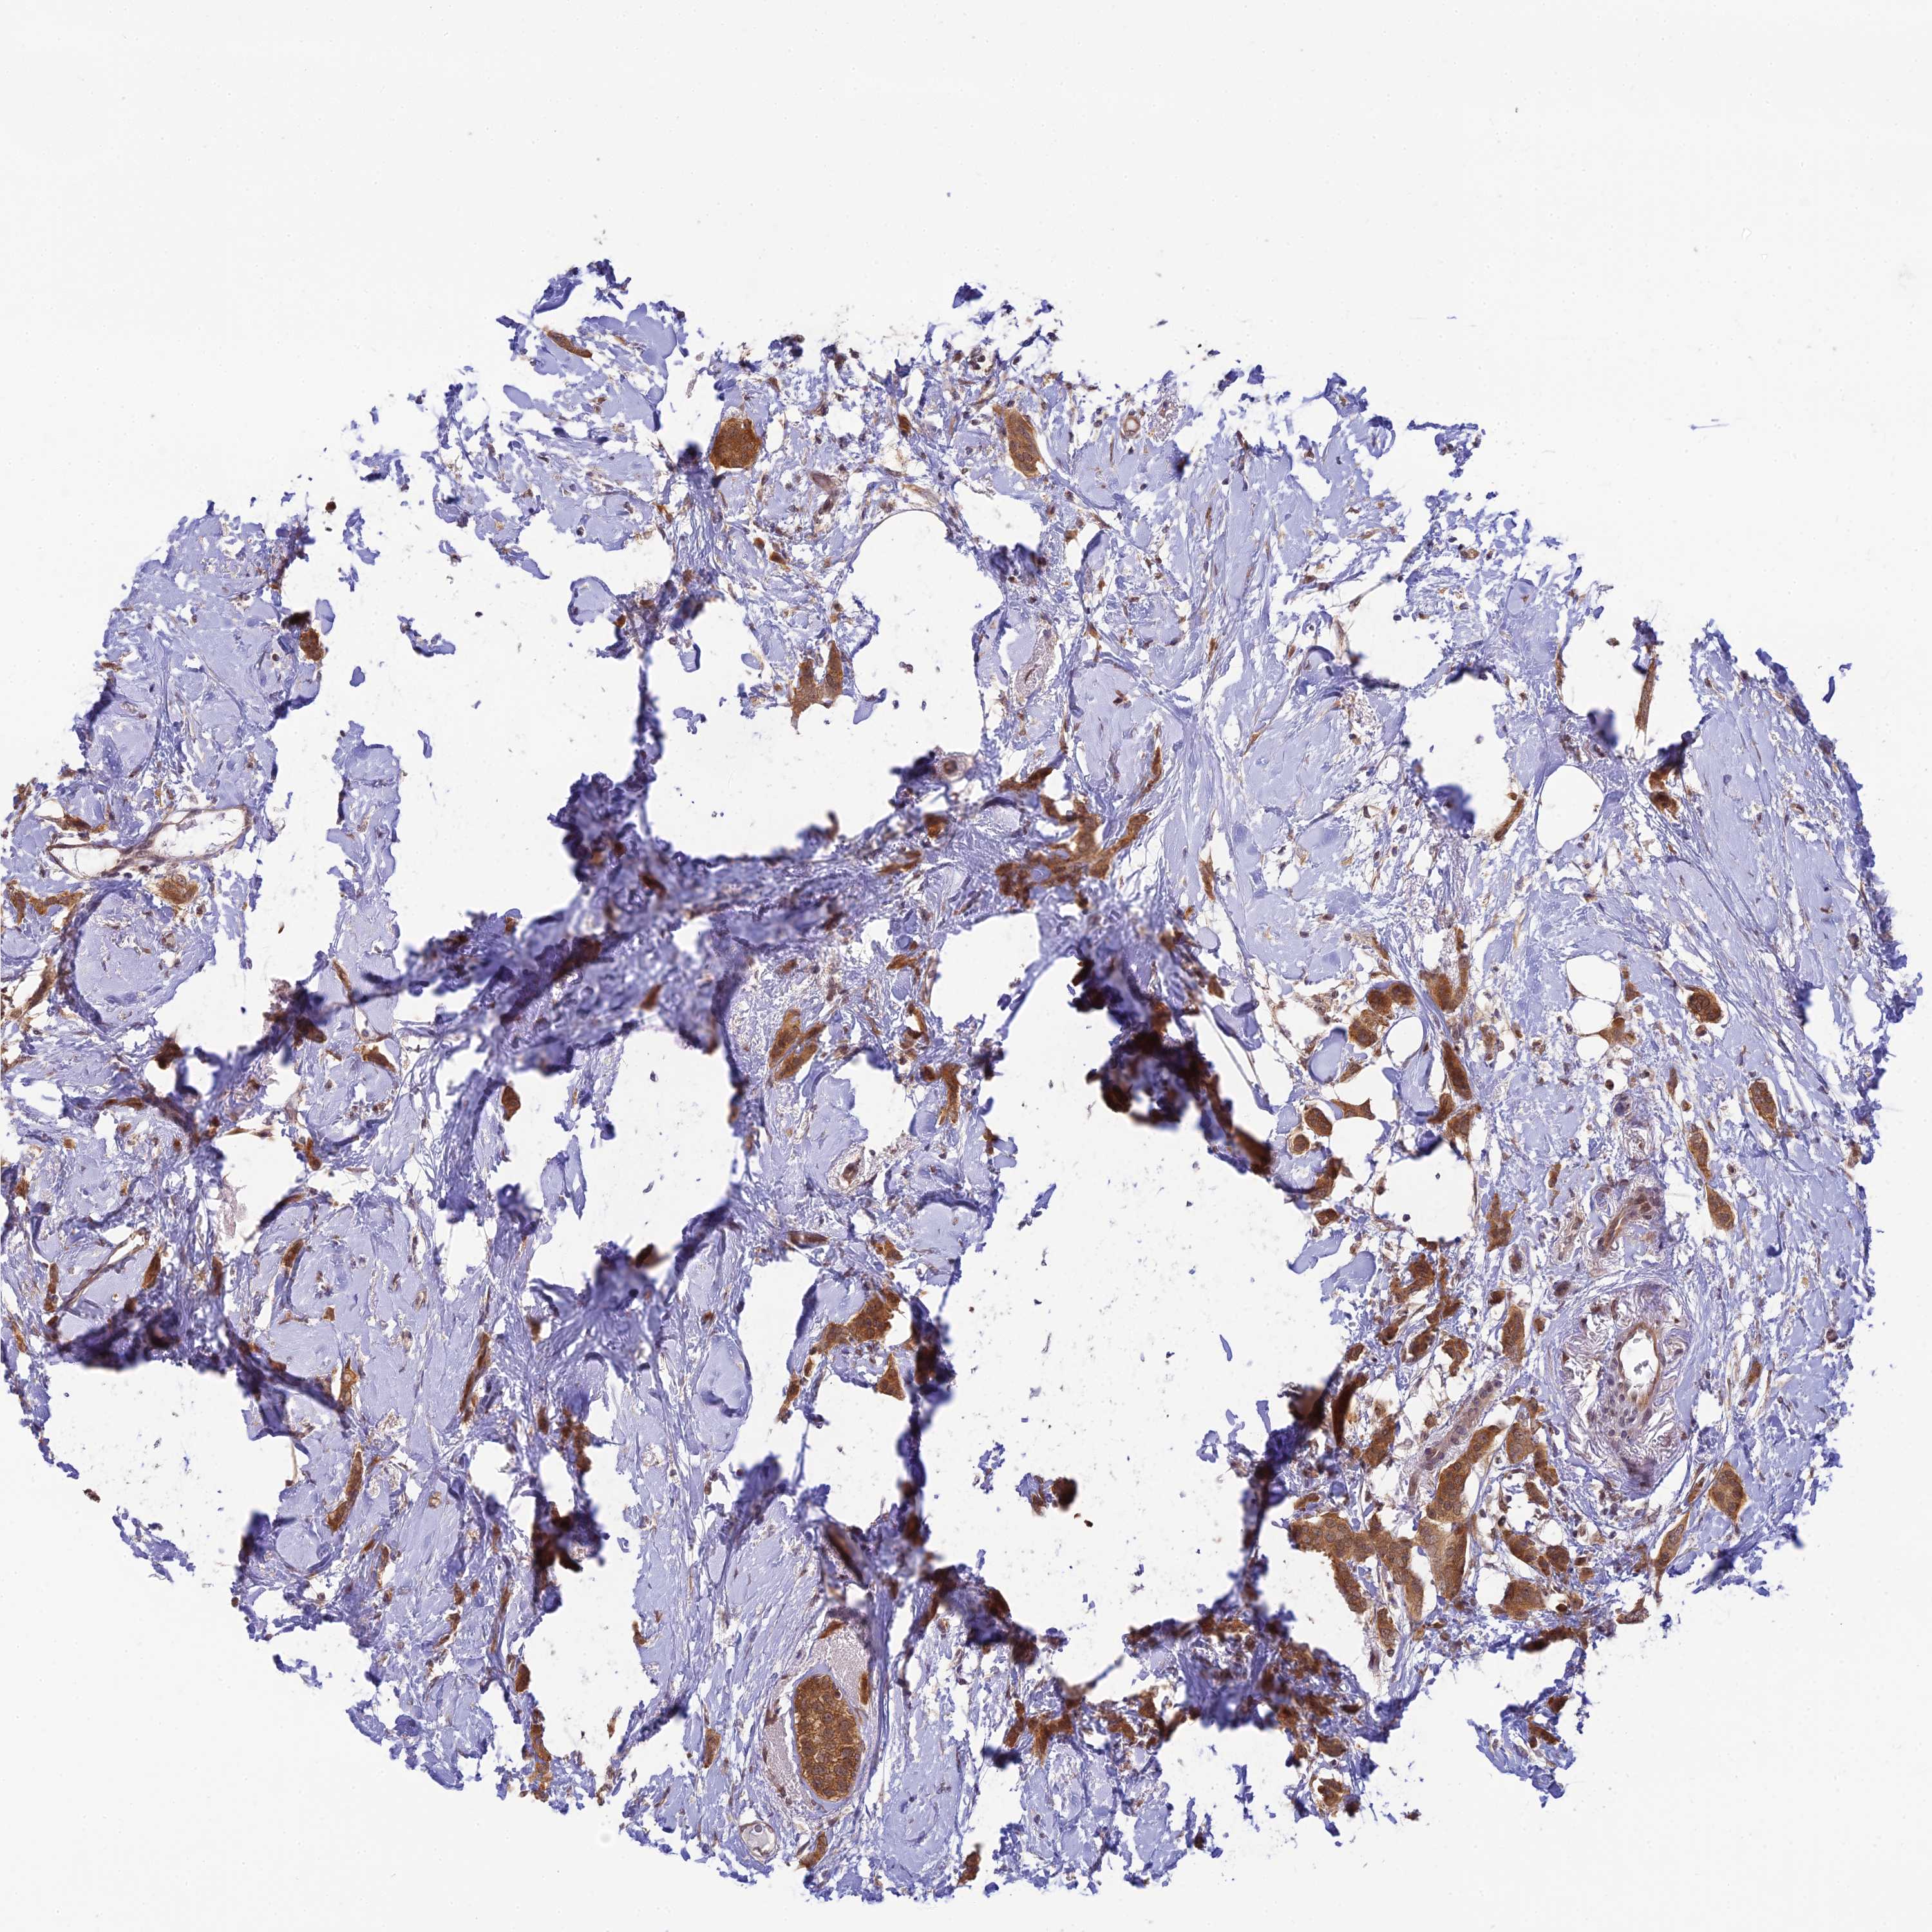

CANCER BREAST CANCER Show tissue menu

BRCA TCGA BRCA VALIDATION PROTEIN EXPRESSION